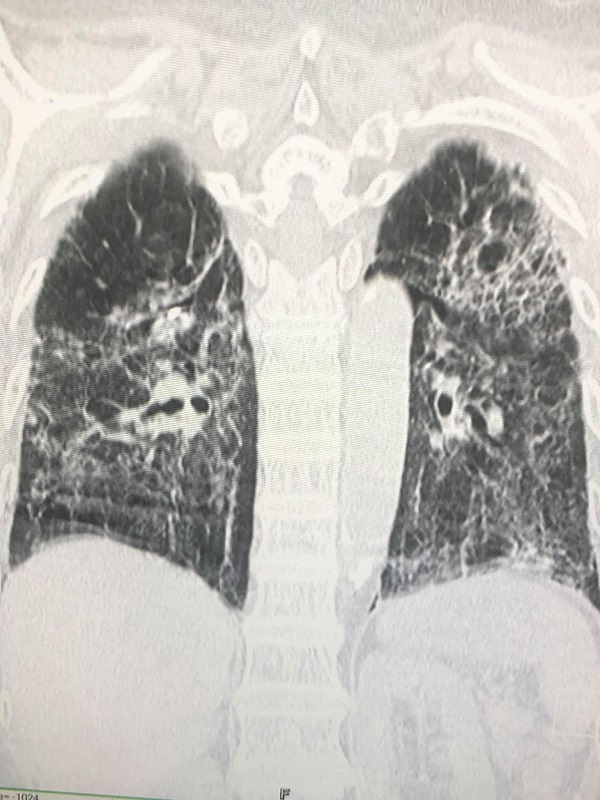

วันที่ 30 กรกฎาคมเหนื่อยมากขึ้นจากปอดข้างซ้ายรั่วเอง ต้องใส่ท่อระบายลม ถอดท่อระบายลมออก วันที่ 9 สิงหาคม ปอดอีกข้างรั่วเอง วันที่ 18 สิงหาคม ต้องใส่ท่อระบายลม วันที่ 23 สิงหาคม ปอดข้างซ้ายรั่วอีก ต้องใส่ท่อระบายลมอีกครั้ง วันที่ 28 สิงหาคม ถอดท่อระบายลมข้างซ้าย วันที่ 31 สิงหาคม ปอดข้างซ้ายรั่วอีก ต้องใส่ท่อระบายลมครั้งที่ 3 วันที่ 2 กันยายน ทำคอมพิวเตอร์สแกนปอดพบพังผืดทั่วปอดร่วมกับหลอดลมเล็กๆโป่งพอง

วันที่ 10 กันยายน ได้ทำการผ่าตัดปอดข้างขวาเพราะปอดขวาไม่ขยายตัวเต็มที่ ด้วยการส่องกล้องเข้าไปในช่องทรวงอกข้างขวา พบถุงลมพองโตที่ผิวของยอดปอดข้างขวาด้านบนและด้านล่าง ต้องตัดปอดเฉพาะส่วนนั้นและเย็บปิด ตัดเยื่อหุ้มปอดด้านขวา ใส่แป้ง Talc เข้าช่องปอดขวา และผ่านท่อระบายลมข้างซ้าย เพื่อให้เยื่อหุ้มปอดข้างขวาและซ้ายติดกัน และส่งชิ้นเนื้อปอดตรวจทางพยาธิวิทยาพบ เนื้อปอดถูกทำลาย มีทั้งอักเสบและพังผืดทั่วไป มีถุงลมพองในเนื้อปอด ขณะนี้ยังต้องใส่ท่อระบายลมทั้งสองข้าง